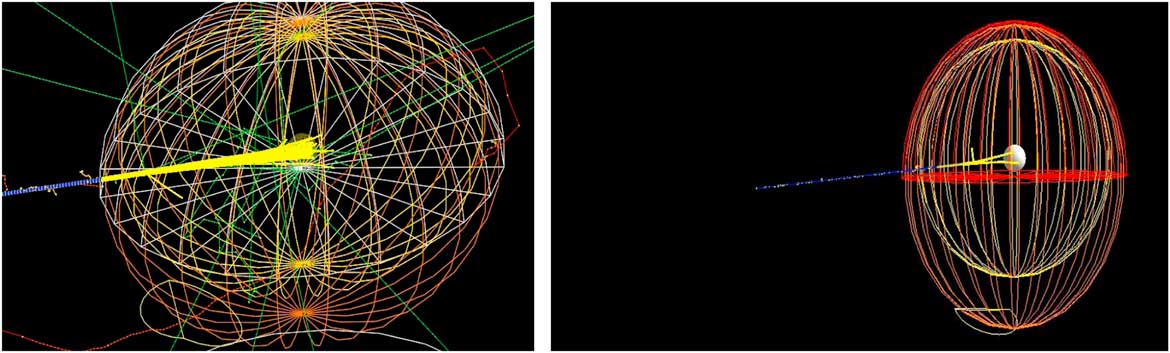

Our main study is to investigate the effect of bio-NMs injected into a tumour during a proton therapy. For this, we have simulated a spherical tumour localised in the centre of a human head. Then, the human head is exposed to a monoenergetic proton beam placed at 1 m from a patient (see Figure 1).

Figure 1 Monte Carlo simulation of 106 beam interaction with a human head.

Proton therapy was simulated with the Monte Carlo code of a tumour within a human head. The tumour is assumed to have a spherical shape with a diameter of 1·5 cm and localised at the centre of the head (see Figure 1). The best way to inject NMs in a tumour localised in a sensitive organ like a human head is by the bloodstream. Carmeliet et al.Reference Carmeliet and Jain 21 and Avnesh et al. (2013)Reference Thakor and Gambhir 22 studied the development of blood vessels in the tumour cells; they noticed that the blood vessels are more concentrated in the centre of a tumour. Consequently, NMs will be distributed with a non-homogeneous way and concentrated more towards the centre of the tumour. In this simulation, the concentration of NMs in the tumour is assumed ranging between 0 and 4%. Figure 2 shows the concentrations of bio-NMs localised in a tumour taken in our simulation.